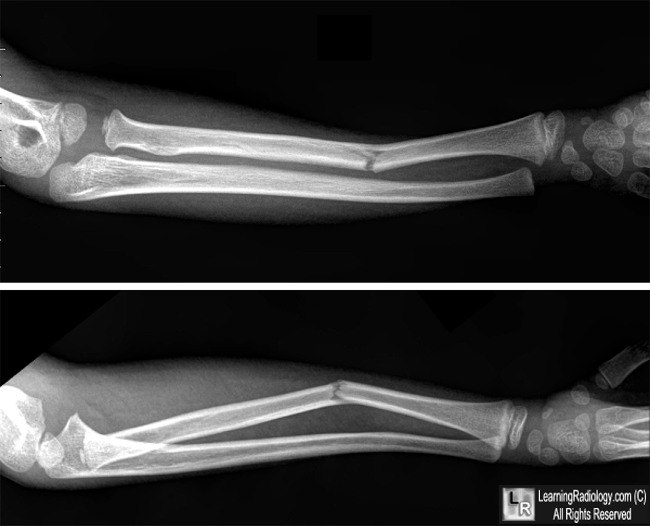

Перелом Монтеджа у ребенка: полное руководство по лечению и восстановлению

Ваш ребенок получил сложный перелом руки с вывихом? Это может быть повреждение Монтеджа. Наша статья поможет разобраться в причинах, симптомах, современных методах лечения и этапах полной реабилитации для возвращения к активной жизни.

Перелом Галеацци у ребенка: полное руководство по лечению и восстановлению

Если ваш ребенок получил перелом предплечья, важно понимать все этапы лечения. В этой статье детский ортопед подробно объясняет, что такое перелом Галеацци, какие методы лечения существуют и как обеспечить полное восстановление функции руки.